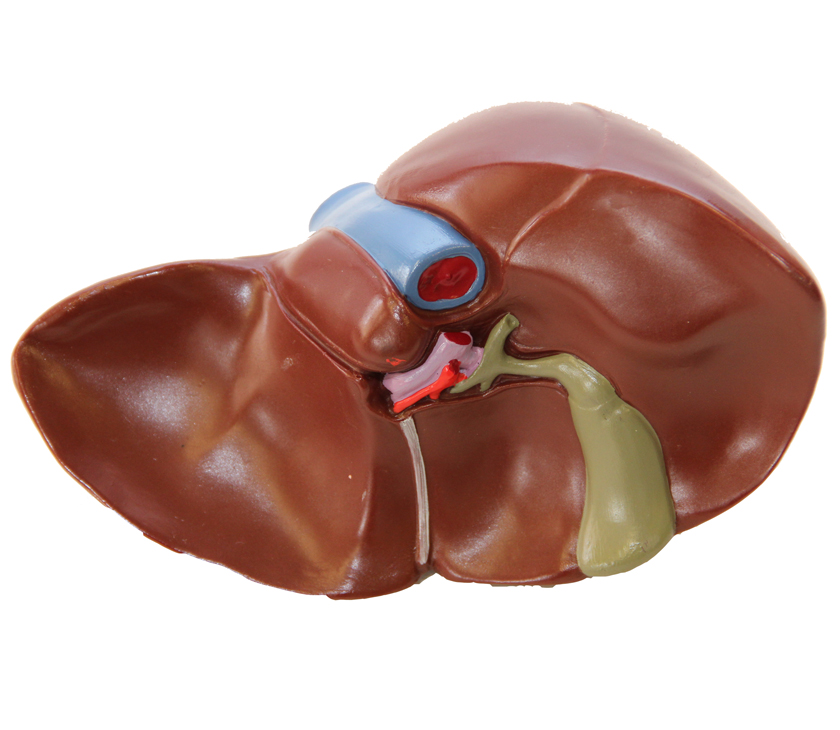

В последние годы в социальных сетях и блогах все чаще встречается необычное явление, известное как “Печень фото”. Этот термин относится к художественному стилю, при котором фотографии печени человека становятся объектом эстетического восприятия и даже искусства. Такие изображения, часто с высоким разрешением и детальной проработкой текстур, привлекают внимание не только медиков и исследователей, но и широкой публики, вызывая удивление и восхищение своей красотой и уникальностью.

Печень фото